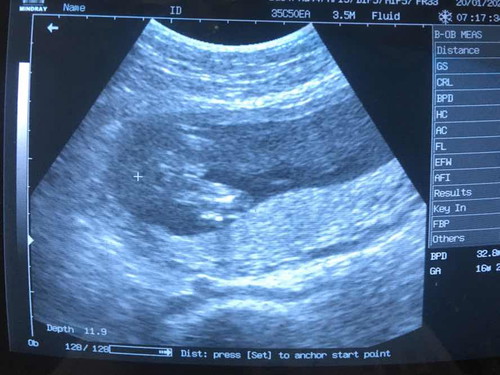

ดูไม่เป็นค่ะ

ญ. หรือ ช. ค่ะ

ให้แม่ไปซาวด์น้องรอบหน้าถามหมอดีกว่าค่ะ ทุกคนจะตอบน่าจะแต่มันไม่แน่นอนเท่ากับหมอบอกหรอกนะคะ เพราะไม่มีเขียนบอกเพศในกระดาษ ดูภาพไม่ออกหรอกค่ะ

ภาพไม่ชัดค่ะแม่ แต่เหมือนจะผช.นะคะ

น่าจะชายมั้ยค่ะ ไม่ค่อยชัด

เหมือนจะเป็นผู้ชายนะคะ

น่าจะชายนะคะ คล้ายๆกัน

เหมือนจะชายค่ะ

ชายค่ะ